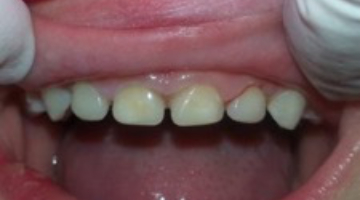

I prep the teeth with a No. 4 or No. 6 round bur, slowly removing decay with short, light touches. Incisal reduction is usually unnecessary, and I avoid it whenever possible. If needed, I use a very fine diamond to refine, shape, and open contacts. I only work two to three seconds at a time and keep a 2×2 gauze under the teeth for children who are uncomfortable with the water spray and suction. Figure 3 shows the final prep.

I apply a self-etching bonding agent, light cure, and fill the strip crowns with Activa BioActive-Restorative. I usually seat the central incisor crowns first, light cure, and then seat the laterals. I remove the strip crowns with an explorer, and very little finishing is required. I use Sof-Lex disks (3M) for the incisal and a fluted carbide at the gingival margin if necessary.

This case took less than 20 minutes and looks great (figure 4). Leigh is pleased with his smile and asked if we could fix more teeth. No anesthesia, no tears, and a happy child looking forward to his next visit to the dentist!